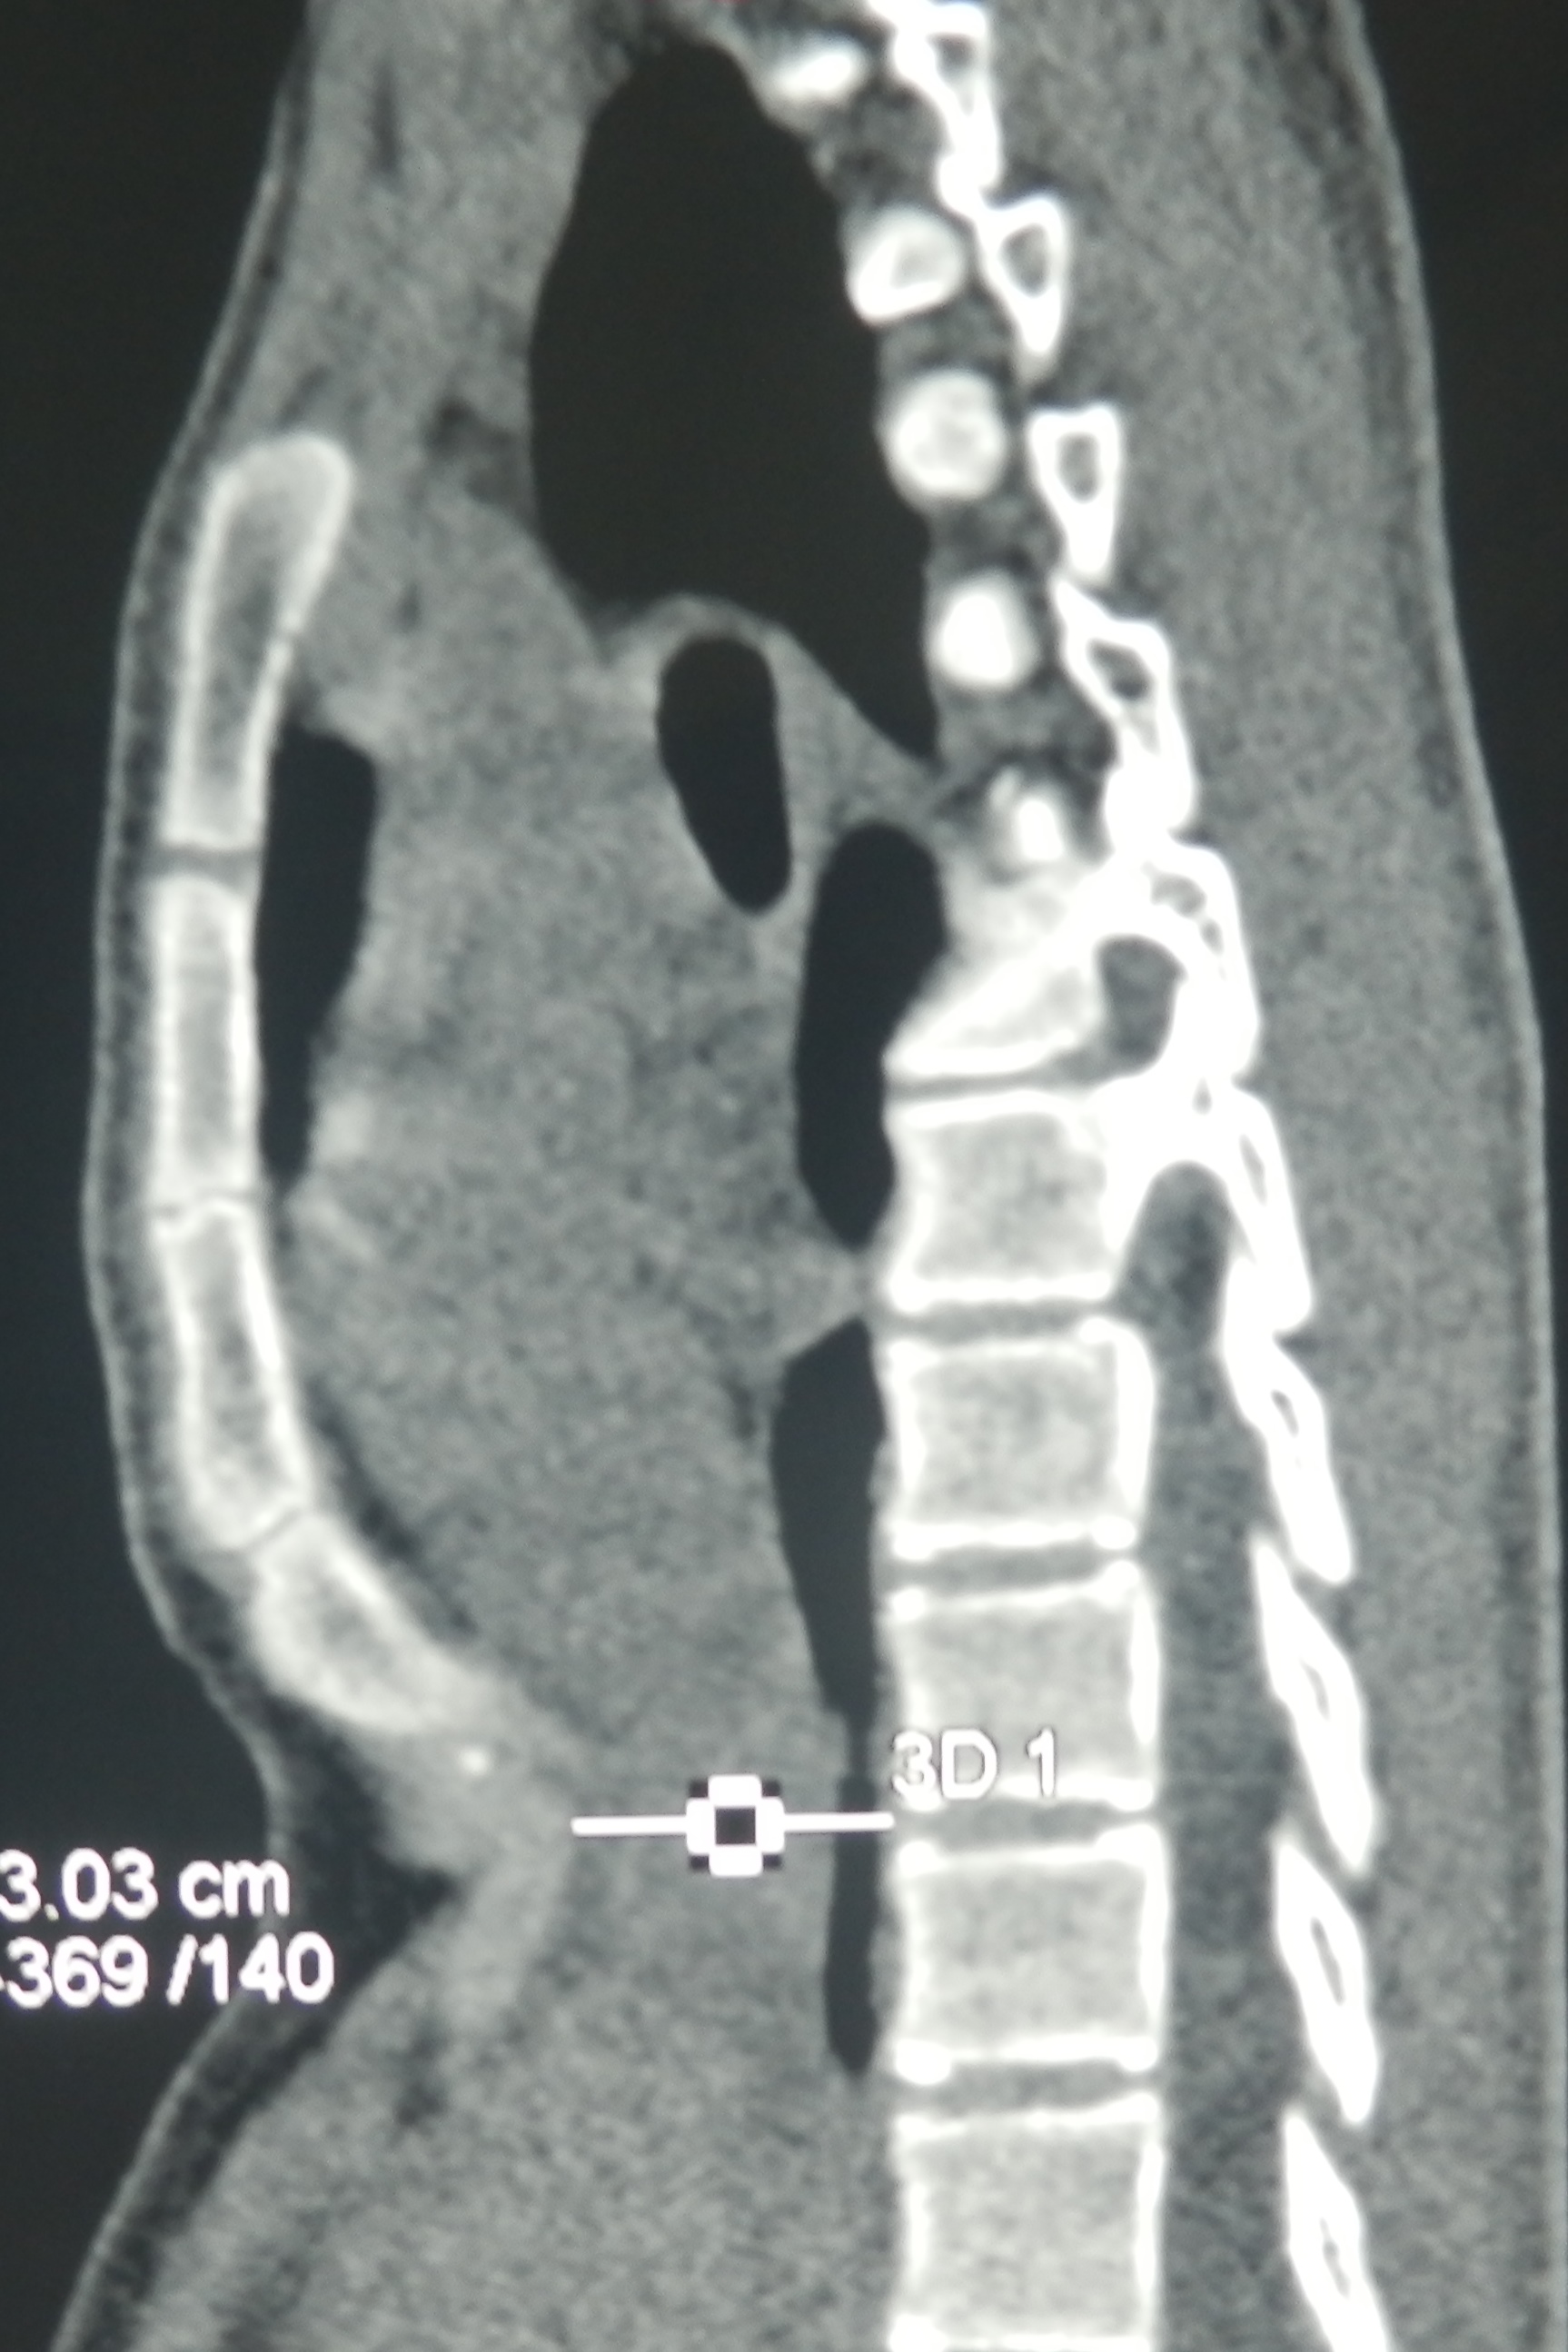

Рис. 2 Компьютерная томография.

При патологии дыхательной системы деток консультирует пульмонолог, назначающий обследование функции внешнего дыхания – спирометрию. Степень выраженности анормальности определяют с помощью метода Галлера – на снимке КТ замеряют фронтальный диаметр и этот показатель делят на сагиттальный. В норме индекс составляет ~ 2,5. Если индекс составляет 3,25 и больше, то болезнь требует хирургической коррекции.

Компьютерная томография грудной клетки до операции наглядно демонстрирует тяжесть воронкообразной деформации грудной клетки

Диагностика воронкообразной деформации грудной клетки осуществляется на основании визуального осмотра, рентгенологического исследования, а также компьютерной томографии грудой клетки с 3D-реконструкцией ребер. Оценивается состояние хрящей, ребер, соединительной ткани (для исключения наличия у пациента синдрома Марфана и других нарушений). Помимо этого диагностика помогает определить степень деформации, центр депрессии, степень смещения сердца. Все эти данные помогаю точнее наметить тактику лечения.

Существует несколько методов количественной оценки тяжести деформации при воронкообразной груди, которые обычно включает измерения расстояния от грудины к позвоночнику. Возможно, наиболее часто используемым методом является метод Халлера, который использует отношение поперечного расстояния до переднезаднего расстояния, полученные на основании КТ. В системе Haller, оценка 3,25 или выше свидетельствует о тяжелом дефекте, который требует хирургического вмешательства.